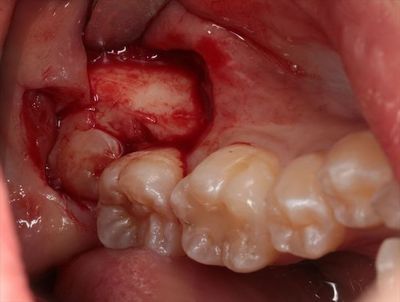

それではいよいよ粘膜を剥離して、抜歯を開始します。

インプラントは粘膜剥離を行わないフラップレスオペを主体で行っていますが

水平埋伏智歯の抜歯の場合は粘膜を剥離せずには不可能です。

IMG_8328_R25.JPG

歯冠と歯根に2分割しました。